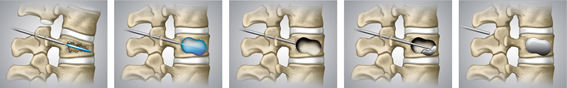

経皮的椎体形成術(Balloon Kyphoplasty: BKP)

骨粗鬆症を伴う脊椎圧迫骨折に対して行われる低侵襲手術の一方法です。この手術手技が適応となるためには幾つかの条件があり、基本的に骨折した椎体の後壁が損傷されていないもの、骨癒合していないものに実施されます。手術は全身麻酔下に背中に約5mmの切開を2ヶ所加えて、細い針を骨折椎体に挿入します。その針を介して風船(Balloon)を骨折椎体内に設置し、膨らますことでゆっくりと潰れた骨を整復します。風船除去後に生じたスペースに骨セメント(PMMA)を注入して、骨折部を固めます。原則、手術翌日より起立・歩行を開始します。入院期間は最短で約7日程度です。